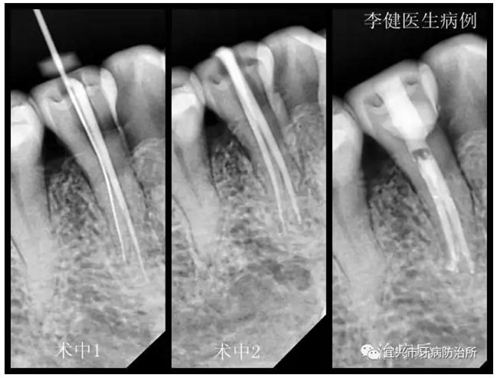

患者,女,55歲,右下前磨牙繼發(fā)齲伴自發(fā)性疼痛前來就診,X線片顯示為雙根管。術(shù)中1選用鎳鈦根管預備銼第一次根管預備未找到,后選用8號細銼在根中1/3處找到另一根管,拍X線片確認。術(shù)中2再次用鎳鈦根管銼預備,并用次氯酸鈉溶液反復沖洗根管。最后利用超聲振蕩機蕩洗根管后,用熱牙膠系統(tǒng)嚴密充填根管,并用樹脂充填窩洞。待后期烤瓷冠修復。